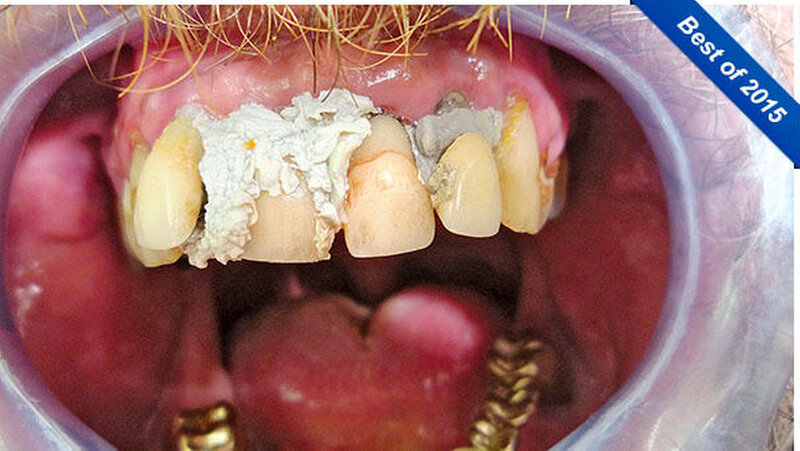

Seine Idee stattdessen: die Zähne selbst zu befestigen. Da er als Handwerker ist er im Umgang mit Baumaterialien versiert ist, sah er sich dieser Herausforderung gewachsen. Er kaufte sich im Baumarkt Fugendichtsilikon und umspritzte damit seine Zähne zur Befestigung. Farblich wählte er "manhattan-grau" und "steingrau" - diese Töne waren billiger als weißes Silikon.

Er achtete auch auf das Biokennzeichen, wie er betonte. Ein halbes Jahr lang war der Patient mit dieser Konstruktion zufrieden. Aber zur Weihnachtszeit gefiel ihm die graue Farbe seiner Silikonbefestigung doch nicht mehr, vielleicht, weil man ihn auch schon auf seine schlechten Zähne angesprochen hatte.

"Er trat nun mit der Bitte an uns heran, alle seine Zähne zu entfernen und ihm doch möglichst eine schöne weiße Prothese anzufertigen. Natürlich mit dem Wunsch, dass alles noch vor Weihnachten fertig wird", schrieben die Zahnärzte. Diesem Wunsch konnte weitgehend entsprochen werden, zumindest was die Entfernung der Zähne betraf.